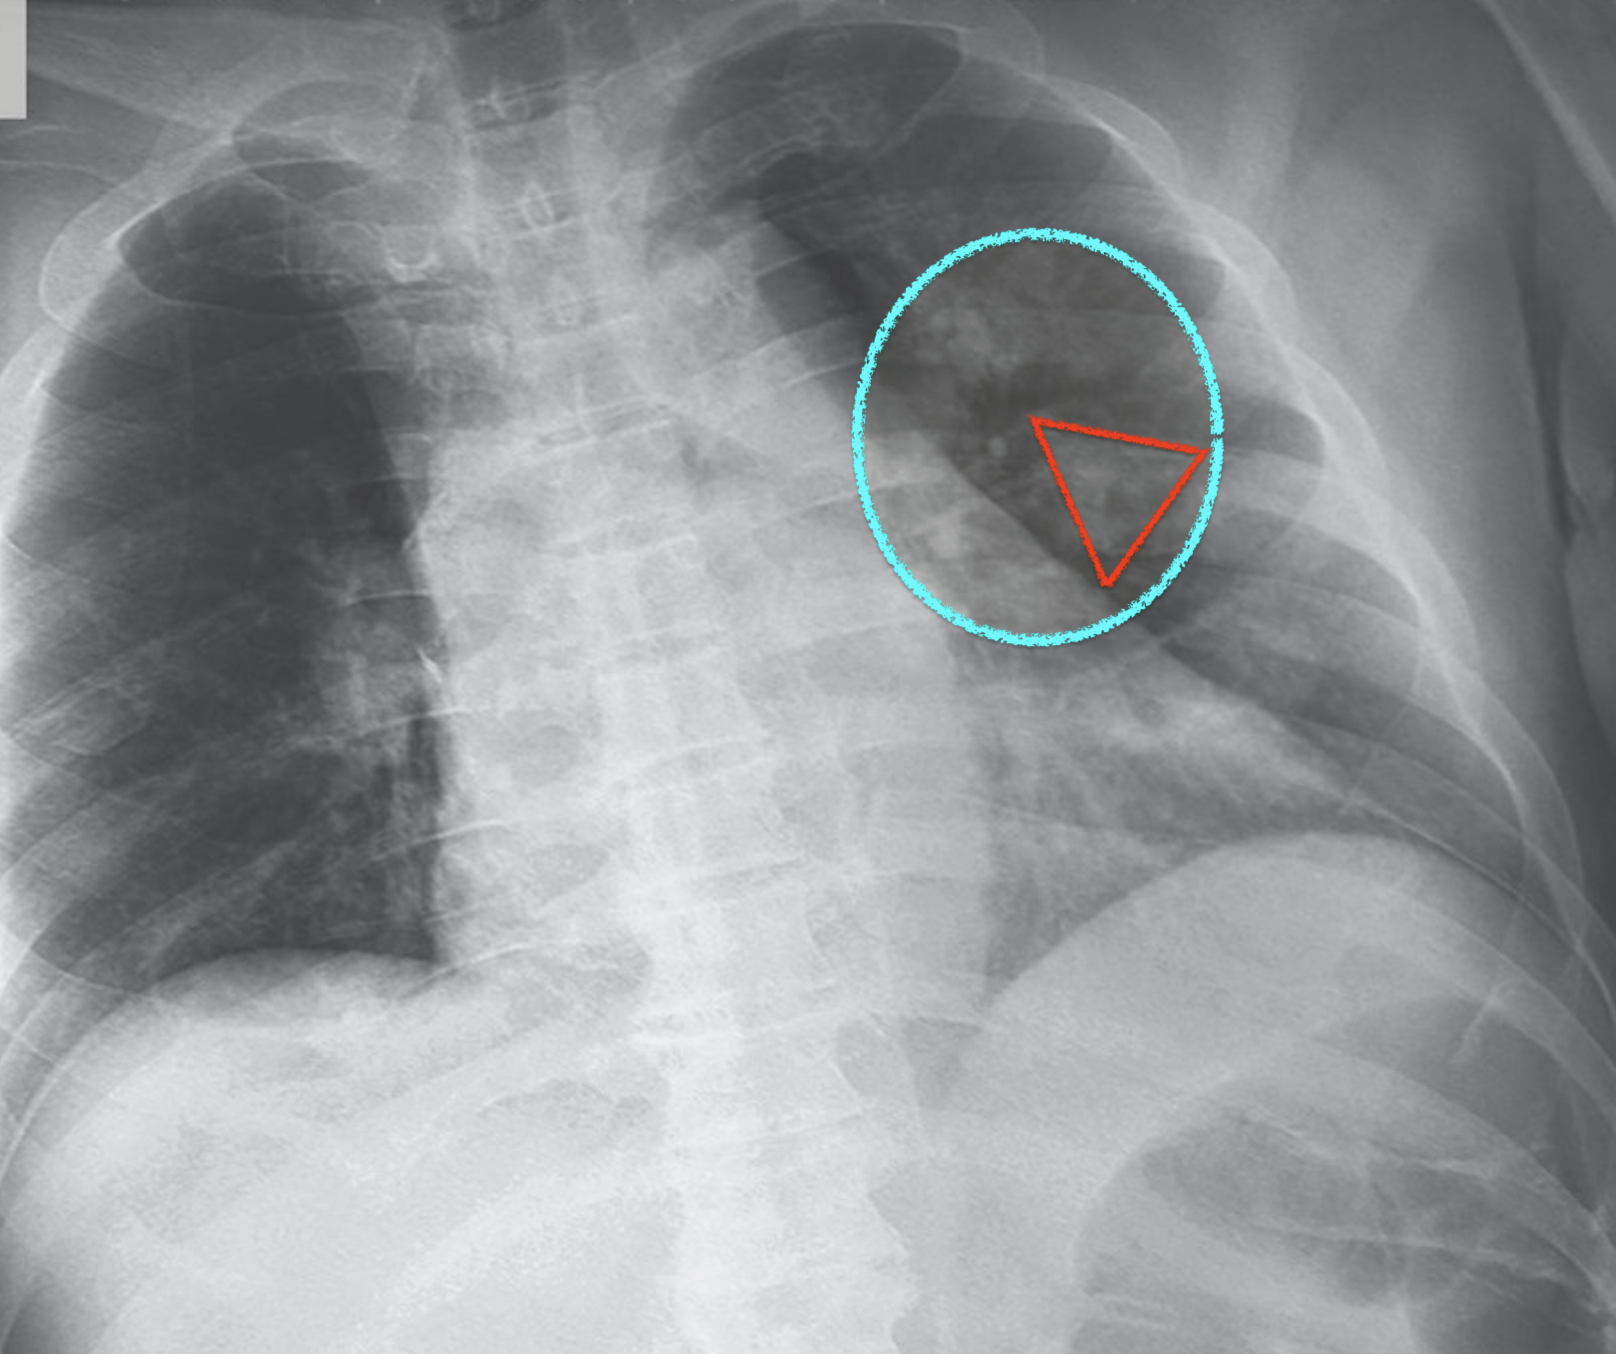

III-D4 Error Analysis

Fig. 6 presents three COVID-19 samples that are classified into Normal, COVID-19, and Pneumonia classes, respectively. X-ray images of COVID-19 patients shows various features for different stages of COVID-19 patients222https://www.uclahealth.orgradiologycovid-19-chest-x-ray-guideline. At the early stage of COVID-19 patients, X-ray images cannot present significant features (Fig. 6 (a)) that can be used to differentiate COVID-19 and Non COVID-19 patients, which leads to the incorrect classification result for the sample. It is consistent with the expectation that X-ray images are not ideal evidences to support diagnosis of COVID-19 for the patients at the early stage.

However, with development of COVID-19, X-ray images are able to present obvious features such as multifocal lung airspace opacities, nodules and consolidation (Fig. 6 (b)), which contributes to the correct classification result. Unfortunately, if the patients are at the late stage of COVID-19, X-ray images presents lobar diffused consolidation (See Fig. 6 (c)) that is similar to features of pneumonia. These features will be confusing to the proposed model and lead to the incorrect result for the sample shown in Fig. 6 (c). In summary, in terms of samples shown in Fig. 6, the proposed model will be effective for the patients who are in the development of COVID-19 rather than those at the early stage or late stage of such disease.